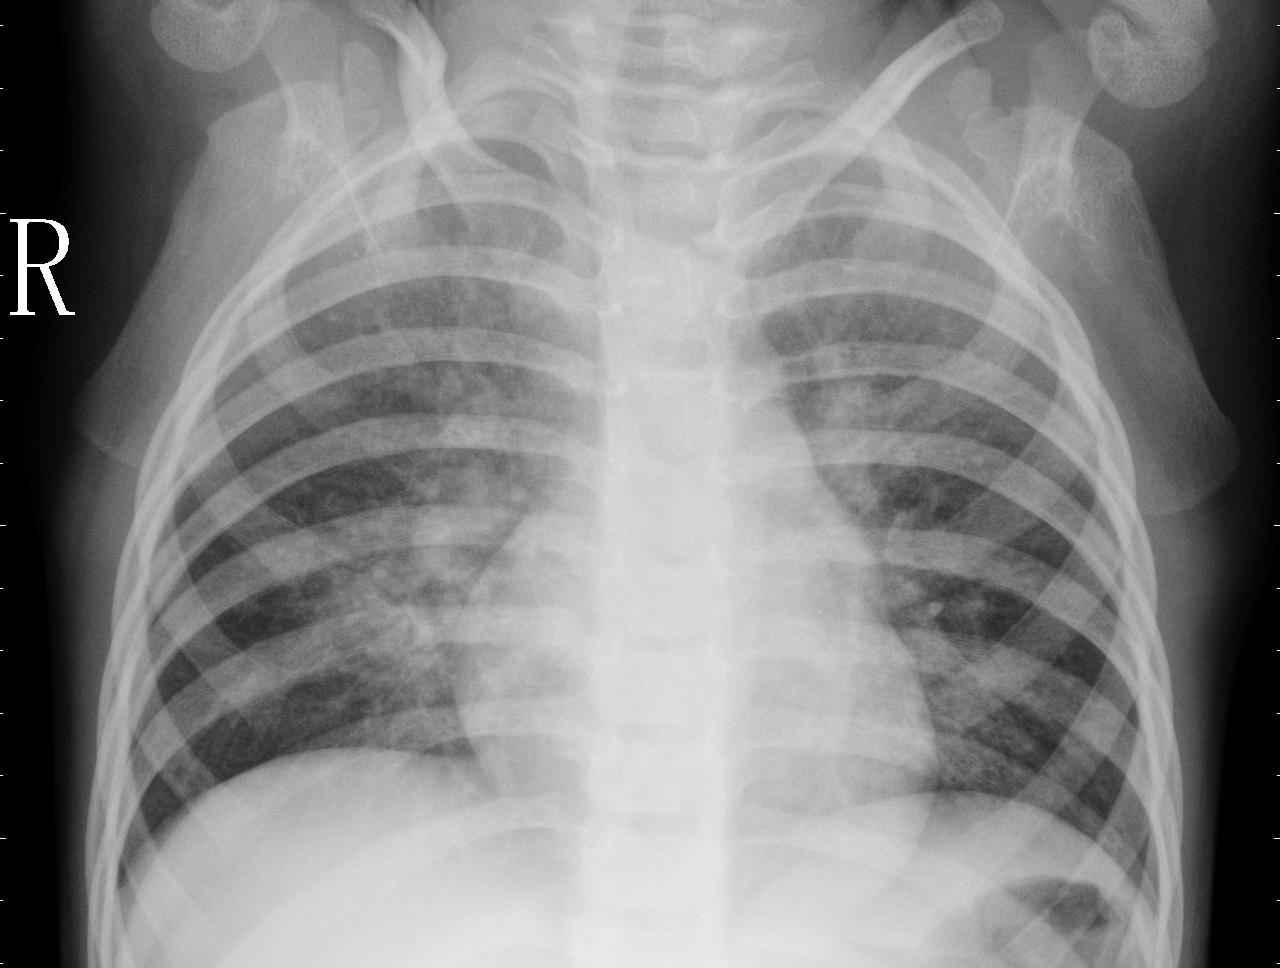

From a radiologist’s perspective, there are key differences between chest X-rays captured from paediatric patients and adult population. First, the size of children’s chest is small compared to adult’s chest, which can also be visible in Figure 4. Second, the rib of children are positioned more horizontally than those of adults as can be seen in Figure 5. Given that children and infants differ, both anatomically and physiology, from adults, these differences have an impact on the clinical assessment using chest X-rays. A learning algorithm can learn these key differences between paediatric population and adult population based on the chest X-rays, leading to model bias as model can report results solely based on these differences rather than radiographic features of a particular disease or abnormality. Hence, we hypothesise not to train model having chest X-rays from mix of both children and adult population. To prove our hypothesis, we run additional experiments to classify COVID-19 vs. Normal (healthy) cases by taking normal cases from different sources. Table 6 shows distribution of normal and COVID-19 cases for binary classification under two settings. For each of the two settings, we split data for each class into training (1106 images), validation (158 images), and testing (316) images, making in total 1580 chest X-rays.

Refer to caption

(a) Adult chest X-ray showing arched ribs

(b) Neonate chest X-ray showing flattened ribs

Figure 5: Differences in ribs positioning visible in chest X-rays from paediatric patients vs. chest X-ray from adult population. Source: https://www.rch.org.au/trauma-service/manual/how-are-children-different/